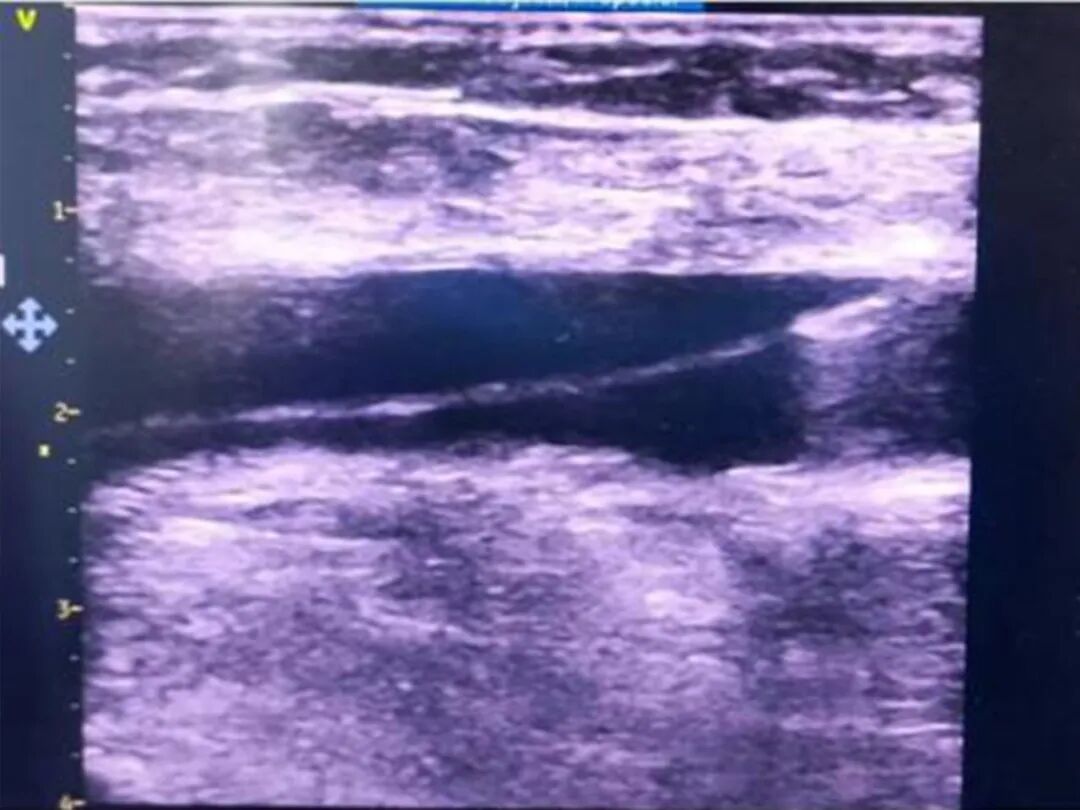

术前心超

• 左房、右房增大,RV:25mm

• 二、三尖瓣轻度关闭不全

• 左室收缩、舒张功能未见异常,EF:52%